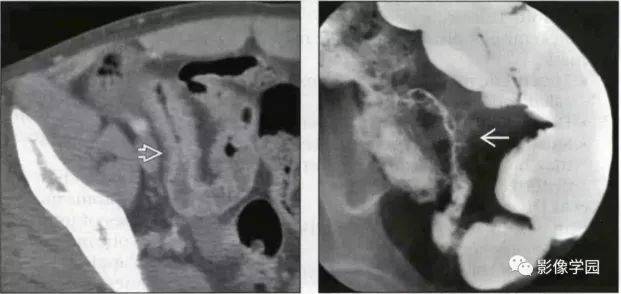

肠道丨克罗恩病及肠结核

胃肠道常见病影像表现胃溃疡消化道肿瘤肠结核

胃肠道结核常继发于肺部结核菌感染:胸部x线检查有助于疑似病例的诊断